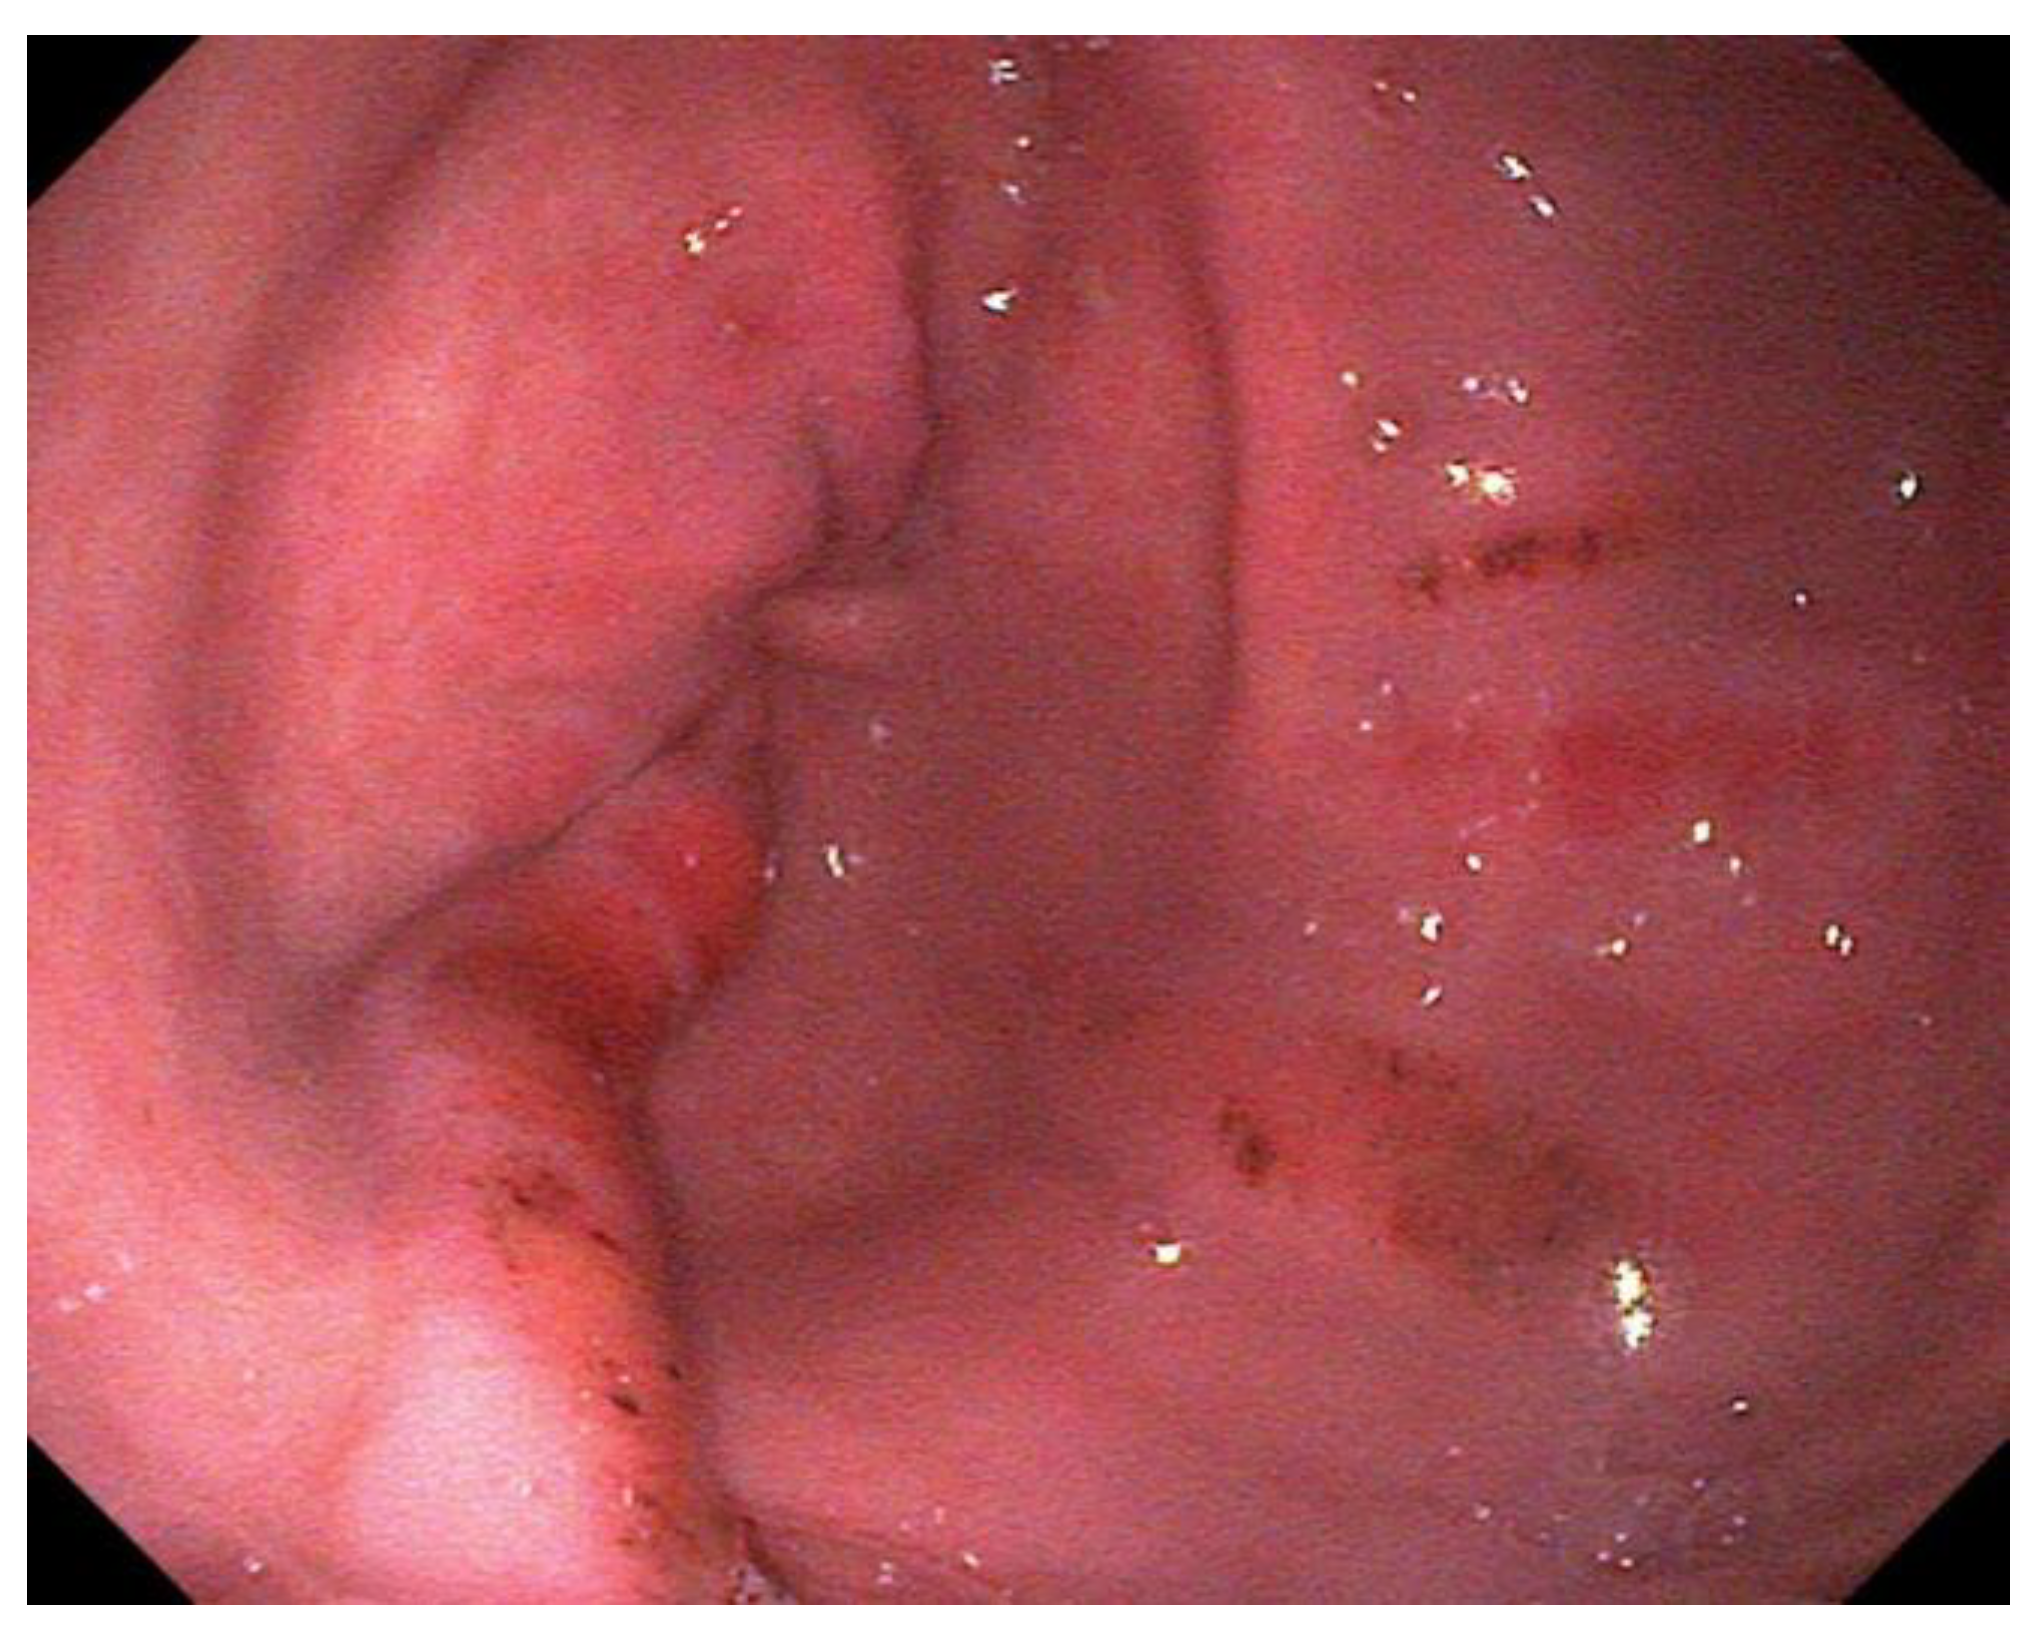

Grading lesions of the squamous mucosa as described by Sykes et al. [1], adapted from Andrews et al. [134]:

- Grade 2 Small, single or multifocal lesions (Figure 2)

Figure 2. Multifocal, hyperemic lesions of the lesser curvature; grade 2/4 ESGD lesions. - Grade 3 Large single or extensive superficial lesions